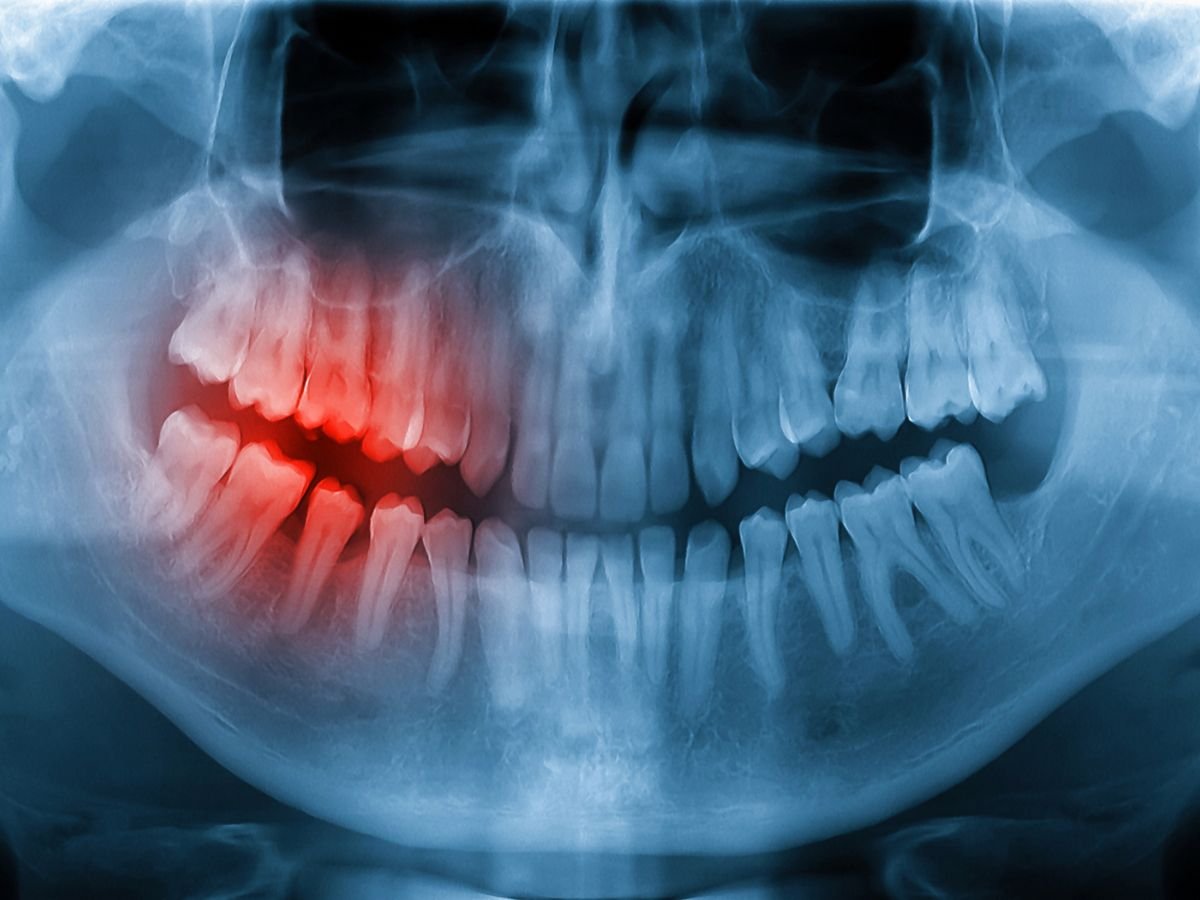

Preventive Dentistry Chart by Oracore Dental in Odenton, MD

Every preventive dental visit includes a comprehensive examination of the teeth, gums, bite, and tissues to detect disease early, use X-rays only when necessary, and monitor oral health changes.